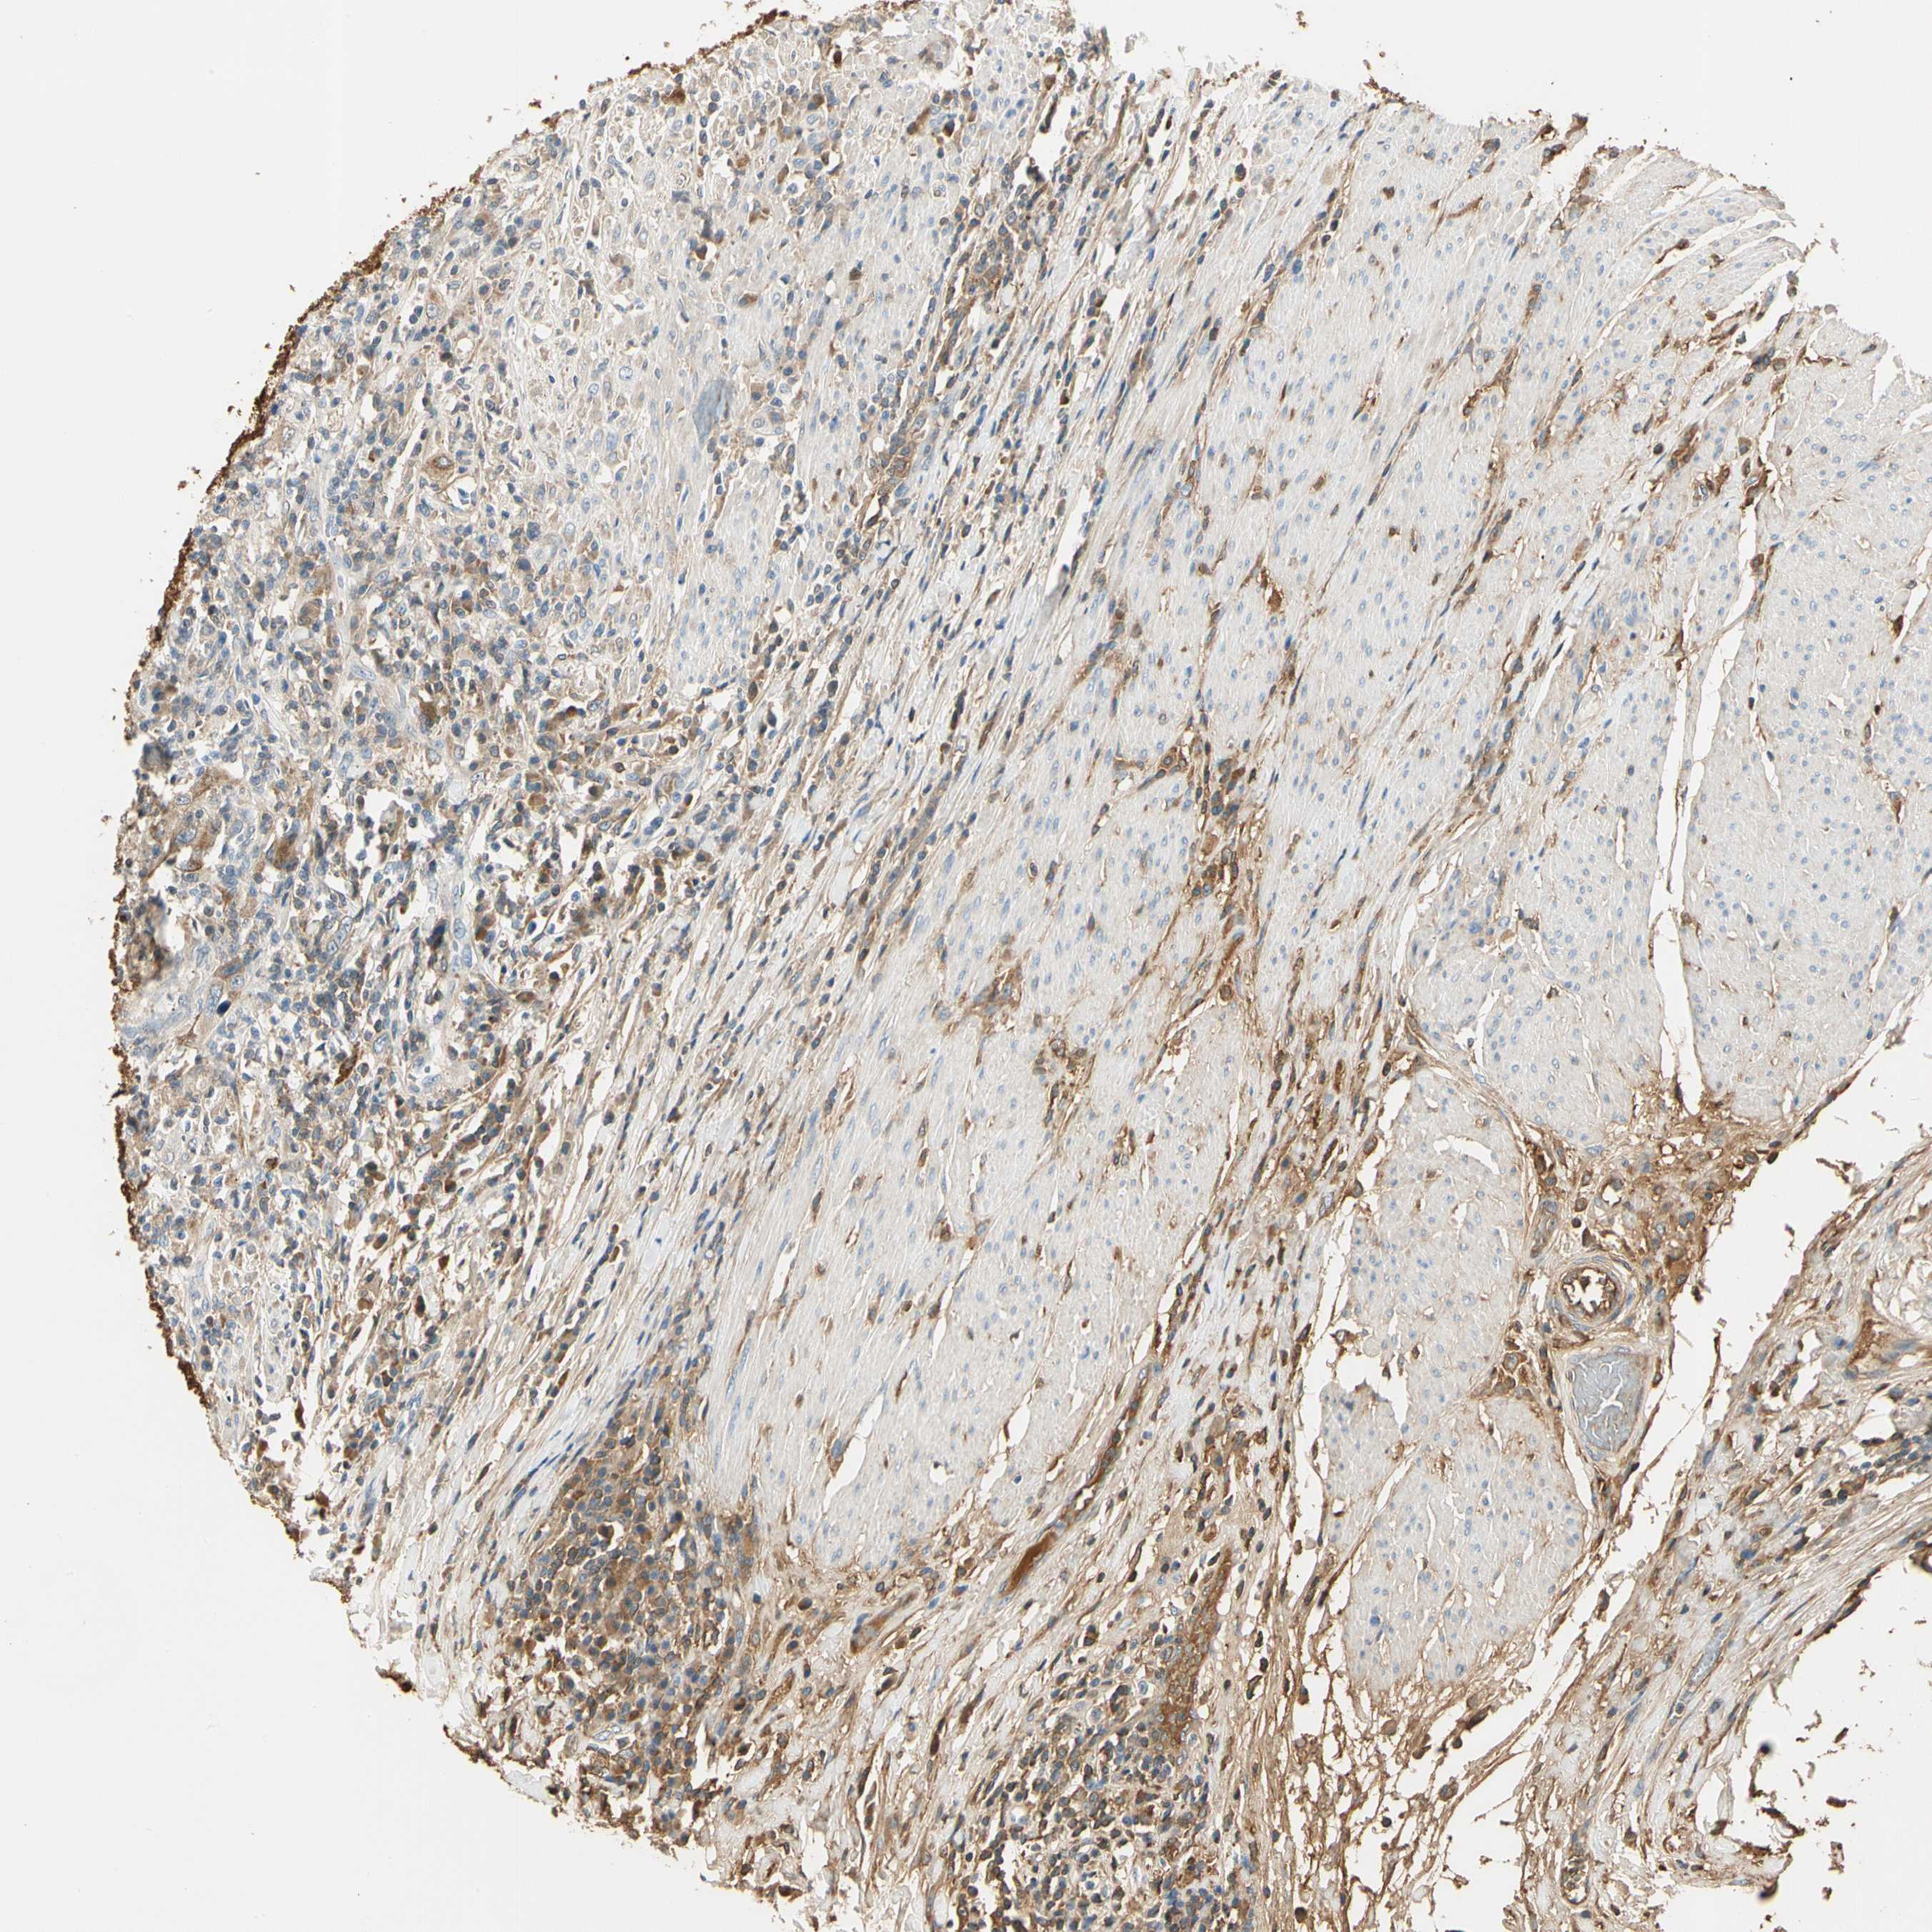

UROTHELIAL CANCER - Protein expressioni

A mouse-over function shows sample information and annotation data. Click on an image to view it in a full screen mode. Samples can be filtered based on level of antibody staining by selecting one or several of the following categories: high, medium, low and not detected. The assay and annotation is described here.

Note that samples used for immunohistochemistry by the Human Protein Atlas do not correspond to samples in the TCGA dataset.

Antibody stainingi

Antibody staining in the annotated cell types in the current human tissue is reported as not detected, low, medium, or high, based on conventional immunohistochemistry profiling in selected tissues. This score is based on the combination of the staining intensity and fraction of stained cells.

Each image is clickable and will lead to virtual microscopy that enables deeper exploration of all samples and also displays staining intensity scores, fraction scores and subcellular localization as well as patient and tissue information for each sample.

Antibody HPA008069

Antibody CAB078183

Staining

High

Medium

Low

Not detected

Intensity

Strong

Moderate

Weak

Negative

Quantity

>75%

75%-25%

<25%

None

Location

Nuclear

Cytoplasmic/membranous

Cytoplasmic/membranous,nuclear

Urothelial carcinoma, Low grade

Urothelial carcinoma, High grade

Urothelial carcinoma, NOS